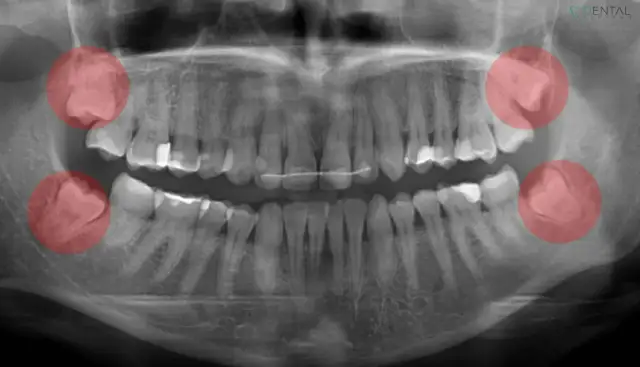

Zastanawiasz się, czy po usunięciu ósemki zęby się przesuną? Ekspert wyjaśnia mechanizmy, ryzyka i korzyści. Sprawdź, jak dbać o zgryz!